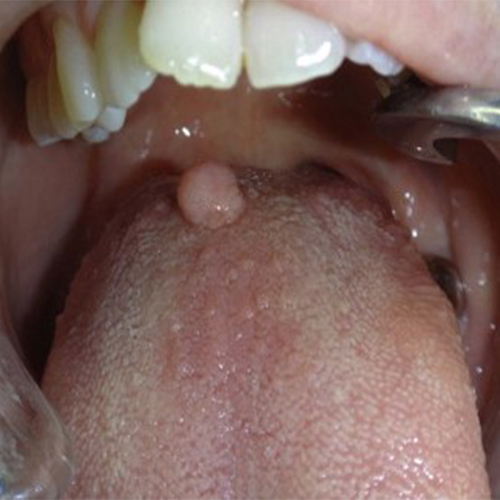

۹) اسکواموس پاپیلوما: یک ضایعه برجسته روی مخاط دهان است که محصول پرولیفراسیون خوشخیم سلولهای اپیتلیالی میباشد. علت آن ویروس پاپیلومای انسانی (HPV) است.

شایع ترین مکان آن مرز کام نرم و سخت است.

رنگ آن اغلب سفید و گاهی صورتی است. خیلی بزرگ نمیشود و صد البته در جوانان بیشتر رخ میدهد.